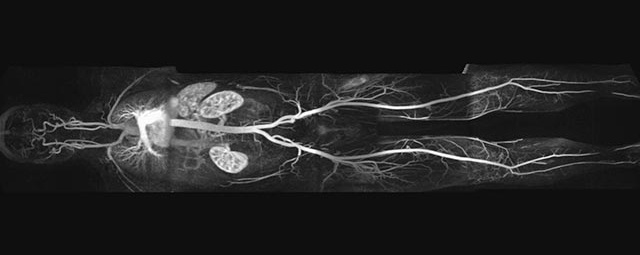

• Bauchgefäße

• Erfassung und Verlaufskontrolle bei arteriellen Aneurysmen (Aussackungen der Arterien), vor allem der Bauchaorta

• Darstellung von Gefäßengen an Nierenarterien, Baucharterien und Becken-/Beinarterien

MR-Angiografie (MRA)

• MR-Angiographie mit Kontrastmittel

• Erfassung arterieller und venöser Gefäße/Bypässe aller Körperregionen mit 3D-Rekonstruktion